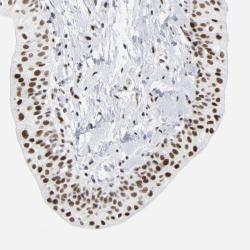

- Experimental details

- Immunohistochemical staining of human urinary bladder shows strong nuclear positivity in urothelial cells.

- Validation comment

- Two independent antibodies targeting one protein yielding similar staining patterns. Staining pattern consistent with experimental and/or bioinformatic data.